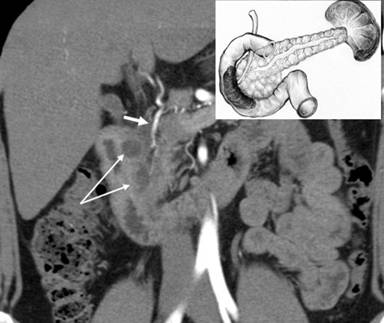

Abdominal ultrasonography did not reveal any significant changes. Contrast multi-detector computed tomography and magnetic resonance imaging showed a fibrous parietal thickening and a large ovoid mass (4.2x2.5 cm) of fluid density, divided by the septa, in the medial wall of the second portion of the duodenum. The pancreatic head, body and tail were unchanged in size and structure. The gastroduodenal artery was shifted notably forward and to the left (Figure 1).

Figure 1. Arterial phase of multi-detector computed tomography (Case #1). Deformation and hardening of the medial wall of the duodenum with a septated cystic structure (double arrow). The gastroduodenal artery is shifted forward and to the left, lying in the groove between the pancreatic head and the duodenal wall involved (short arrow). The scheme of the lesion and the unaffected pancreas is in the upper right corner. |